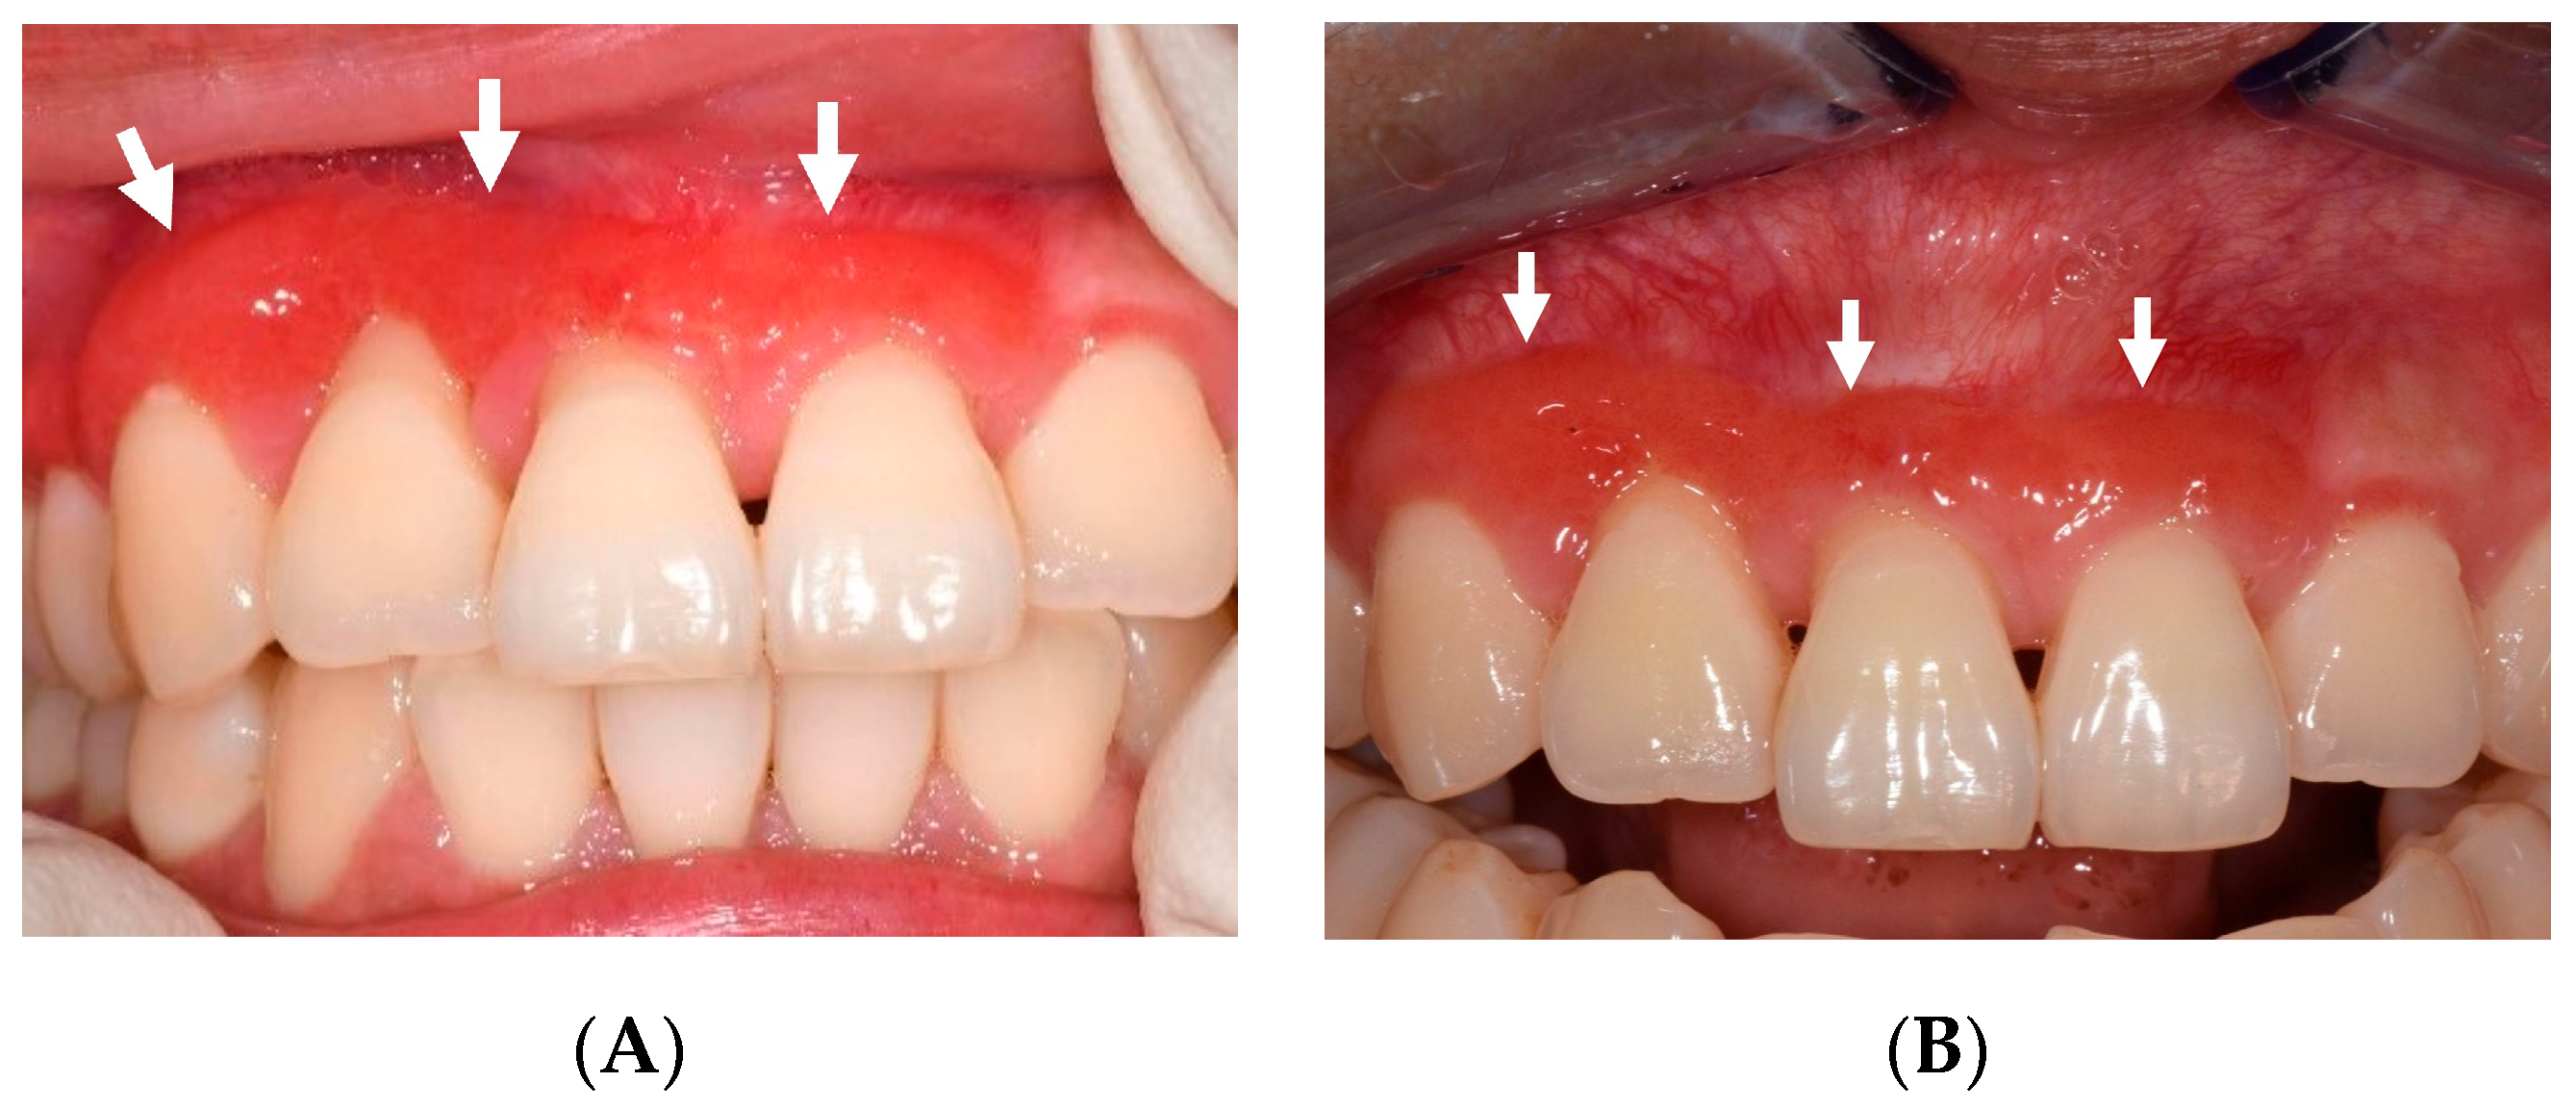

By March 2023, all previously affected areas had fully mucosalised, although the buccal attached gingiva of her upper right first premolar to upper left central incisor remained erythematous and spongy, with no associated deep-probing depths (Figure 4A). Buccal recession around her upper central incisors was observed.

Figure 4.

(A) Twelve-month follow-up showing erythematous and spongy buccal gingiva (white arrows). Buccal gingival recession is evident. (B) Eighteen-month follow-up showing reduction in size of spongy buccal gingiva (white arrows).

Oracort E® (triamcinolone acetonide 0.1%, lidocaine hydrochloride 0.3%) was prescribed, but the patient discontinued use after two days, as she found the texture uncomfortable. The spongy erythematous lesion at the buccal of the upper right canine to upper left central incisor was still present at the 18-month review but had decreased in size (Figure 4B).

Creeping attachment of the previously receded buccal gingiva of the upper right lateral and central incisors was observed despite the remaining presence of black triangles at the area. The lesion was tender to palpation but otherwise asymptomatic. The lesion will be monitored closely at regular reviews. A detailed timeline can be found in Figure 5.